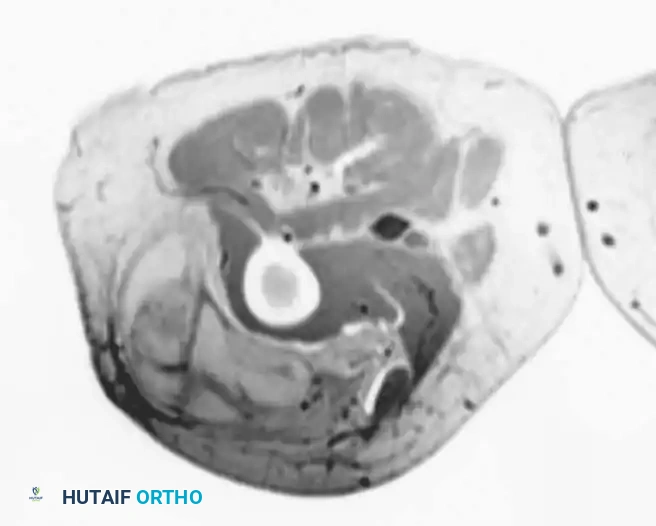

MRI is highly specific for well-differentiated variants, demonstrating fat signal intensity (bright on T1, suppresses on STIR/Fat-Sat) with thick, nodular septations.

T1-weighted MRI of a well-differentiated liposarcoma (atypical lipoma) of the thigh.

Contrast-enhanced, fat-suppressed axial MRI of the same lesion. Note the multiple thick, enhancing septa distinguishing it from a benign lipoma.